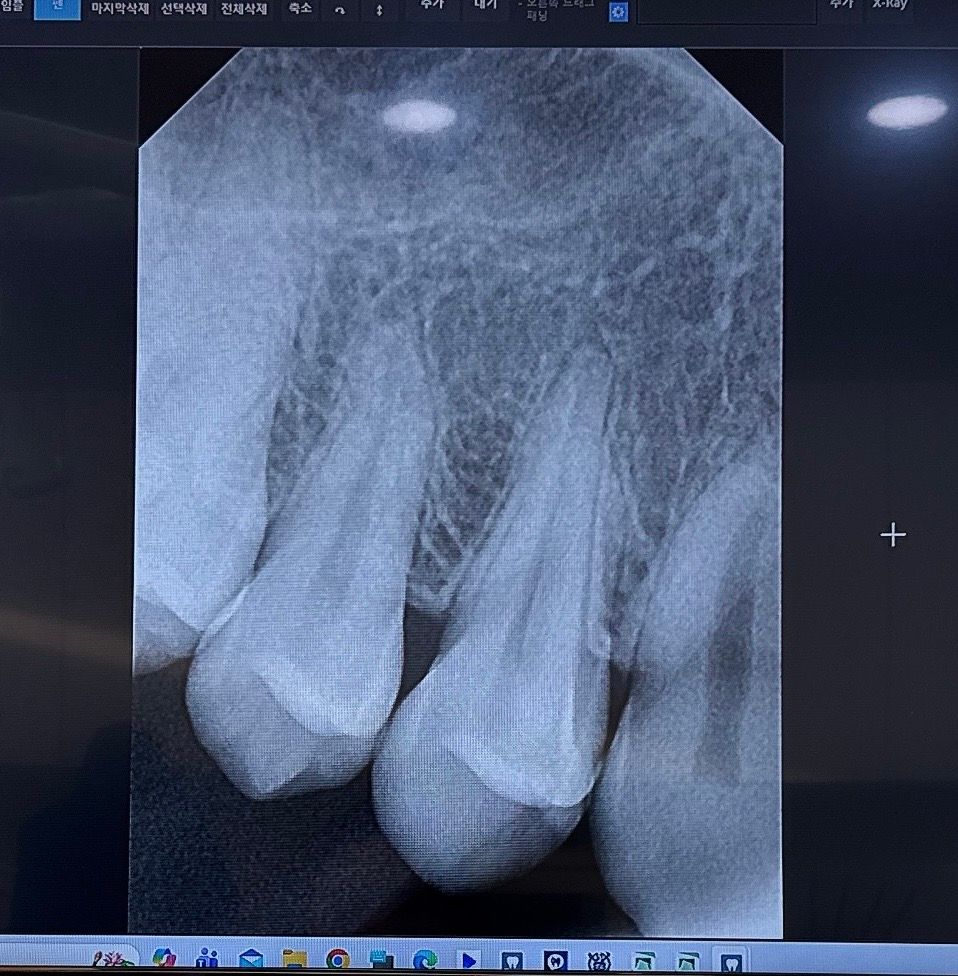

치아 엑스레이 이상없는지 한번 봐주세요

저번에 치아를 자꾸 흔들어서 통증이나 시림이나 찌릿함이 생겨서 오늘 치과에서 그냥 딱딱한거 씹고 자주 만져서 통증이 생겼다고 말씀드리고 엑스레이찍었는데 금이나 염증은 없어서 일단 더 지켜보자 하셨거든요 지금 엑스레이상으로는 뿌리손상이나 치아손상이 또는 잇몸상태에 문제있는지 궁금합니다 ㅜㅠ 만약 괜찮으면 걱정안해도 될까요?? 꼭 양쪽 치아 확인 부탁드립니다!!

치아, 뿌리, 잇몸 괜찮으니 염려 안해도 될것같습니다. 치아에 자극을 주지 않도록 하면 좋을것같습니다. 건강하세요.

x-ray 상에서 이상이 없습니다. 흔들거리는 느낌은 일시적으로 잇몸이 들뜨면 그럴 수도 있지만 저절로 좋아집니다.